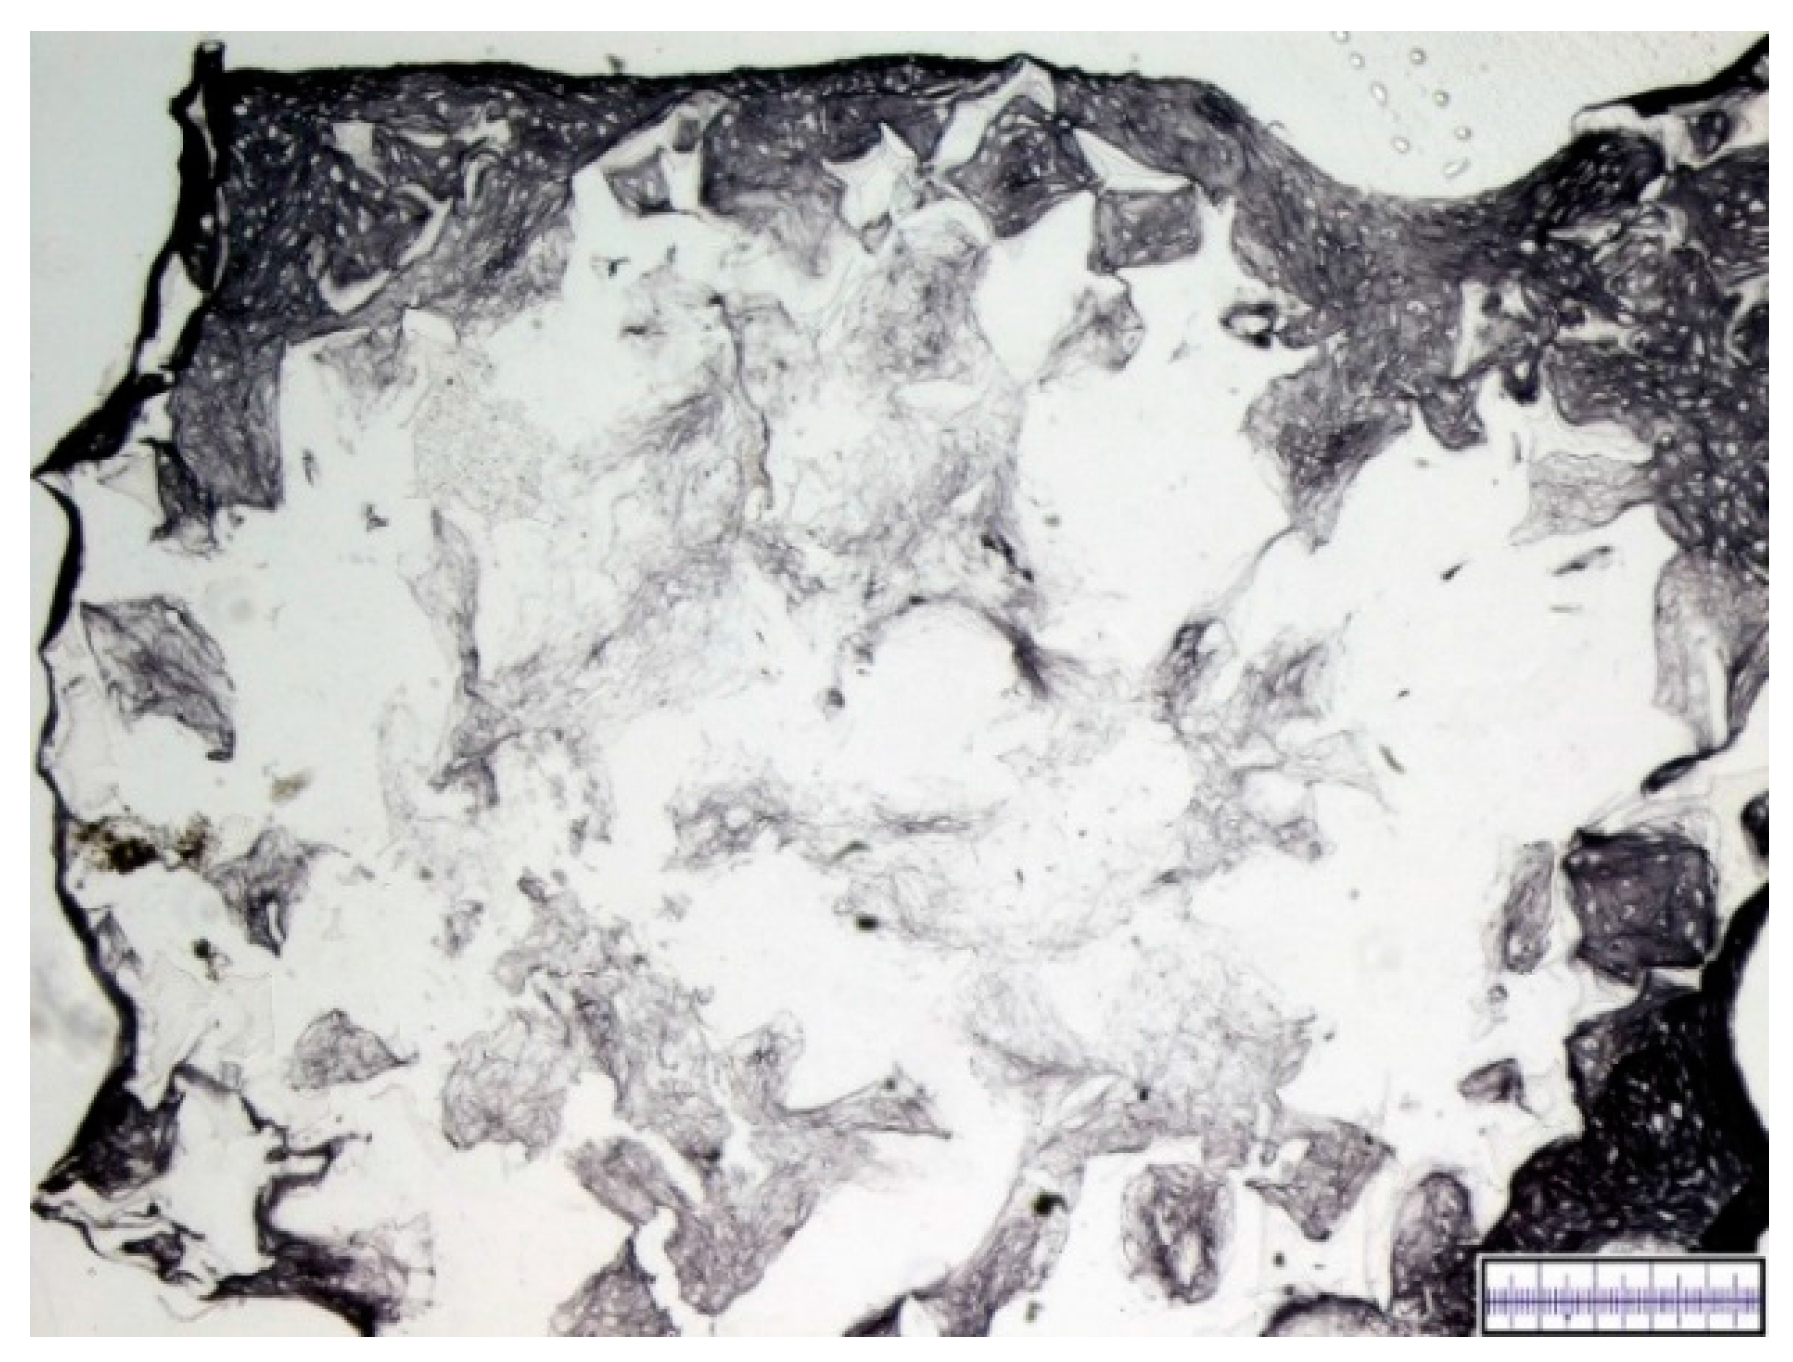

3.1. Macroscopical Assessment of Scaffold Pore Structure

3.2. Interconnectivity of Scaffold Pores